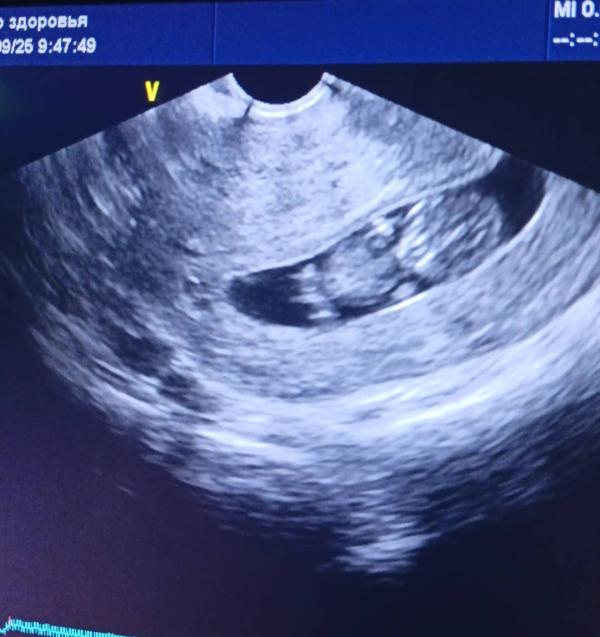

Сходила на УЗИ, и врач зачем-то сказала, Наверно на скрининге скажут пол!

КТР 32мм

Сб до 155мм

Прикрепление по задней стенке.

Шейка длинная.

Всё соответствует сроку.